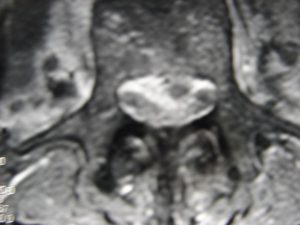

Εικόνα 3 (α,β,γ,δ,ε,ζ)

Μαγνητική Τομογραφία της Ο.Μ.Σ.Σ. (13/06/2007) Ακολουθία Τ1 και Τ2

Οβελιαία τομή (α,β) Παρατηρείται η ύπαρξη Επισκληριδίου Αποστήματος στο επίπεδο Ο3-Ο4 που προκαλεί μεγάλη στένωση του σπονδυλικού σωλήνα, με απώθηση του νωτιαίου σάκου. Διαπιστώνεται επίσης η ύπαρξη παρα-σπονδυλικού αποστήματος

Εγκαρσία τομή (γ,δ) Παρατηρείται η ύπαρξη Επισκληριδίου όπως επίσης και προ-παρασπονδυλικού αποστήματος.